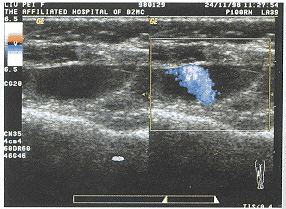

中国超声医学杂志991232 患者女,19岁。自诉2年前因右膝部血管瘤行手术治疗。术后右膝部逐渐又形成肿块,并缓慢长大,伴阵发性搏动性疼痛。查体:右膝部扪及质韧包块,边界不清,表面颜色较正常皮肤稍暗。临床诊断为血管瘤复发。彩超所见:右膝偏内侧探及3.6cm×1.7cm×3.9cm大小团块,边界不清,内见较多条索状无回声区,粗细不一,部分相互连通。CDFI:团块内无回声区充满红色及蓝色血流信号(图1),PW探及静脉型血流频谱。该团块右侧探及3.9cm×1.1cm±4.2cm大小无回声,边界较清晰,边缘探及不规则中低回声。CDFI:无回声区内可见自前壁射向后壁的彩色血流回声(见图2),呈搏动性,PW探及脉动性血流频谱,Vmax 33.0cm/s,RI 0.80。彩色血流信号周边可见充盈缺损。彩超诊断为:①右膝内侧混合性蔓状血管瘤;②右膝偏外侧假性动脉瘤伴瘤内血栓形成。手术及病理证实诊断。

图1 血管瘤边界不清,内见丰富红色、蓝色彩色血流回声。

图2 假性动脉瘤内可见彩色血流回声从前壁射向后壁,周围见中低回声。